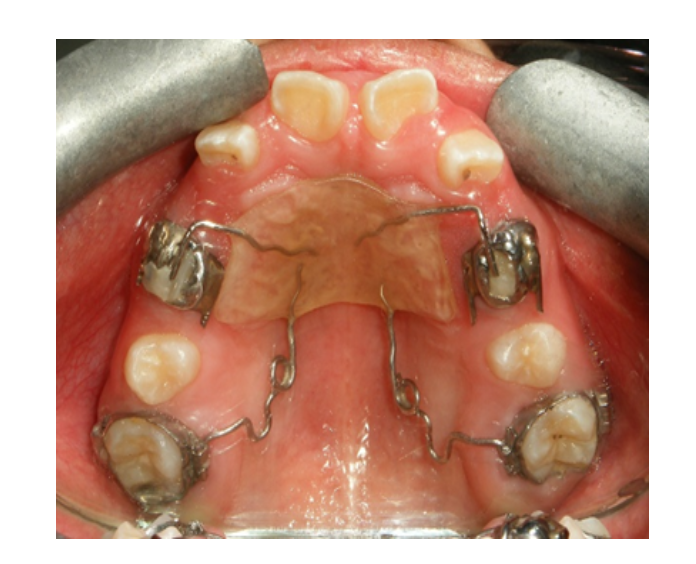

Ortodoncia

temprana

Ortopedia facial